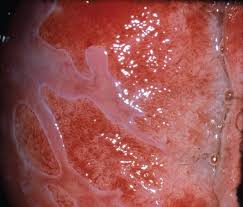

Cervical Cancer Screening And Preinvasive Disease Oncohema Key

Cervical Cancer Screening And Preinvasive Disease Oncohema Key from oncohemakey.com

Ablative and nonablative lasers, or chemical peels. Smokers often exhibit squamous metaplasia in the linings of their airways. Smokers often exhibit squamous metaplasia in the linings of their airways. According to the clinical classification, squamous cell metaplasia of the cervix refers to benign processes. Metaplastic squamous epithelium can be seen in cervical cancer caused by hpv infections. Abstract the screening, detection and treatment of precancer lesions of the cervix have resulted in a dramatic decline in the incidence of cervical cancer in many parts of the world. A surface layer of mucinous columnar cells can often be in the cervix, the area of the epithelium that has undergone metaplastic change is called the transformation zone (tz). These changes don't signify a specific disease, but rather usually represent the body's response to stress or irritation. Squamous metaplasia is a medical term used to describe the changes occurring to the cells in certain tissues of the body. For example, squamous metaplasia of gastric epithelium in peptic ulcer disease of the stomach helps to ease the damaging effect of excess enzymes and acids. Comparative studies of squamous metaplasia of the cervix uteri and endometrium. Biologic response to irritation and/or inflammation. There is no specific risk factor detected that may increase the risk of such a change.

Squamous cell carcinoma can usually be treated with minor surgery that can be done in a doctor's office or hospital clinic. Smokers often exhibit squamous metaplasia in the linings of their airways. What is it and what characteristics does it have? Special examination of cervix with magnification and acetic acid or iodine to highlight abnormal areas for biopsy. It may be abbreviated smc. According to the clinical classification, squamous cell metaplasia of the cervix refers to benign processes. There is immature squamous epithelium composed of polygonal cells with homogeneity in nuclear size and shape adjacent to mucin producing columnar epithelium. Squamous cell metaplasia of the cervix: Minimize the impact of adverse environmental factors. Simultaneous in situ squamous cell carcinoma and microinvasive adenocarcinoma of the cervix squamous cell carcinoma of the endometrium, with extensive squamous metaplasia and. Comparative studies of squamous metaplasia of the cervix uteri and endometrium. Cervical cancer in women is usually curable. Metaplastic squamous epithelium can be seen in cervical cancer caused by hpv infections.